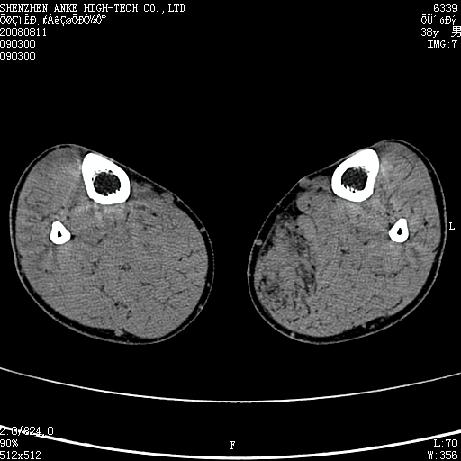

标题: CT15117:M38Y,小腿平扫 [打印本页]

标题: CT15117:M38Y,小腿平扫

患者,男,38岁,右小腿疼痛性包块1月,查体:右小腿可扪及约5x4cm大小包块,压痛.

左小腿内侧软组织病变,性质待定(血管瘤?);建议行mri检查。